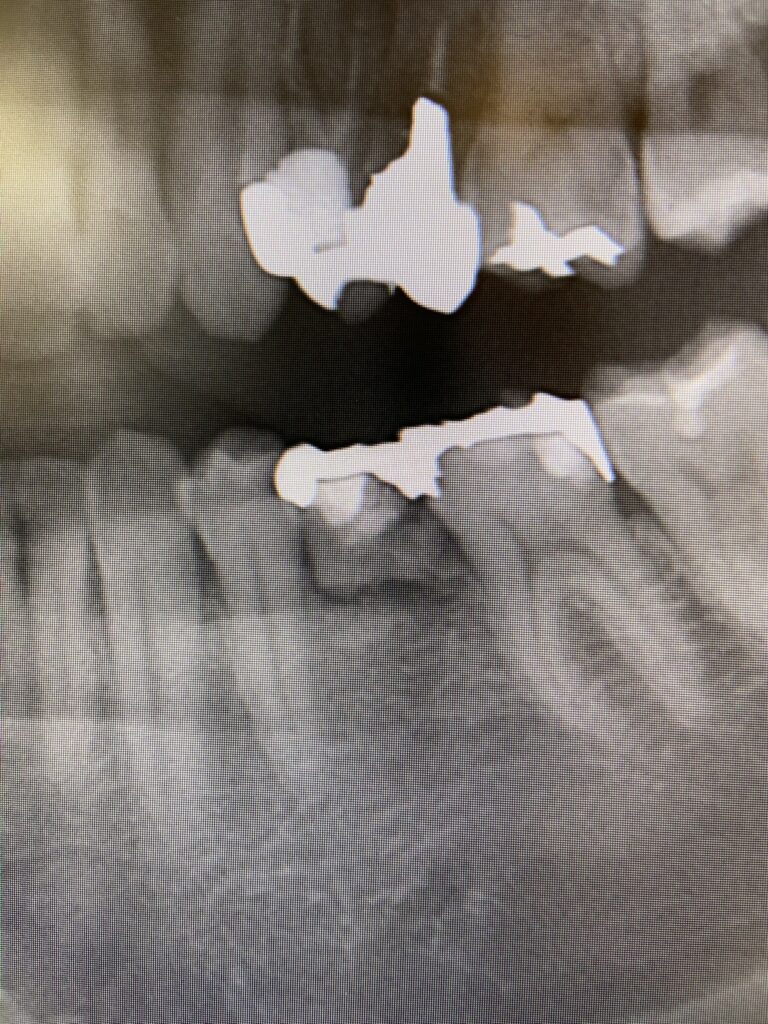

虫歯の治療では、虫歯菌に侵された部分をしっかり削り取らなくてはなりません。

もし虫歯が浅ければ、削る範囲も小さくすみます。しかし虫歯が深く進行していた場合、どうしても「神経の近くまで削る」必要が出てきます。

歯の中には「象牙質」という層があり、そのさらに奥に「歯髄(神経)」があります。象牙質には無数の細い管(象牙細管)が走っていて、外部からの刺激がこの管を通って神経に伝わります。虫歯が深く、神経近くまで削った場合には、この象牙細管を通じて冷たい刺激や熱い刺激が神経に届きやすくなり、結果として 治療後の「しみる症状」 が出やすいのです。

つまり、多くの場合は時間の経過とともに神経が落ち着いてしみなくなりますが、中には症状が強くなり、神経を保護しきれなくなるケースもあります。その場合には、追加治療として「神経を取る(根管治療)」が必要になることもあります。